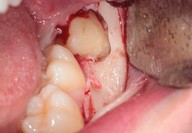

Galleria fotografica